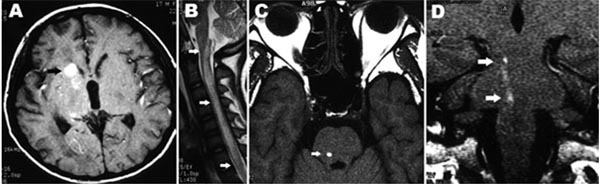

Chẩn đoán hình ảnh về thần kinh [53][55],[84],[85] trên 11 bệnh nhân có bệnh lý GĐGTTK được báo cáo trên y văn. Chụp CT sọ não, xuất huyết dưới nhện và xuất huyết nội sọ là các hình ảnh hay gặp. Trên một bệnh nhân phát hiện có xuất huyết dưới màng cứng. Dấu đặc trưng của bệnh lý giun đầu gai ở não trên phim chụp MRI là phát hiện vết xuất huyết (track). Dấu hiệu cộng hưởng từ của thương tổn xuất huyết thay đổi tùy theo các tổn thương thể cấp, bán cấp và mạn tính. Do đó, trên hình ảnh T1 và T2 cả giảm tỷ trọng và tăng tỷ trọng đều phát hiện. Không thấy di chứng gradient-echoT2 được báo cáo. Tuy nhiên, dấu hiệu này rất nhạy với các các khối máu tụ tại chỗ không đồng nhất và có thể trở thành một chuỗi tiếp nối trong đánh giá chẩn đoán hình ảnh của bệnh giun đầu gai thể não.

Sưng phồng tủy sống đa đoạn lan tỏa kèm theo tăng tỷ trọng T2 là hình ảnh hay gặp nhất trên chụp tủy sống. Tăng gadolinium của các thương tổn được báo cáo trong phim MRI chụp sọ não và tủy sống của 4 bệnh nhân như là hình ảnh nốt, sáng và đồng nhất.

Bảng 6. Đặc điểm chẩn đoán hình ảnh trên thần kinh của bệnh giun đầu gai thể thần kinh

Vị trí | Phương thức chẩn đoán | Phân tích hình ảnh trên hệ thần kinh |

Não bộ | CT | Nhu mô não (đơn điểm hoặc đa điểm) tăng tỷ trọng vùng dưới màng cứng hoặc dưới màng nhện tương ứng với xuất huyết trong não |

| MRI | Đa điểm (giống giun) tăng tỷ trọng T2 hoặc giảm tỷ trọng trong cả hai bán cầu não và tiểu não đường kính ≥ 3mm (vệt xuất huyết) có hoặc không có tăng thành phần gadolinium. |

Tủy sống | MRI | Dãn hoặc sưng phồng tủy sống kèm theo tăng tỷ trọng đa đoạn T2, thường tăng ngấm gadolinium (nhẹ đến trung bình) trên hình ảnh sau tiêm chất cản quang T1 |

* CT_CTomputed tomography; MRI: Magnetic Resonance Imaging |